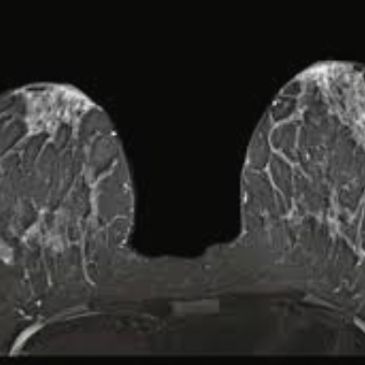

Principle: Combines T1/T2-weighted sequences, DWI/ADC mapping, and dynamic contrast-enhanced imaging to evaluate vascularity and permeability (Ktrans).

Advantages:

Limitations:

Performance:

Clinical Role: